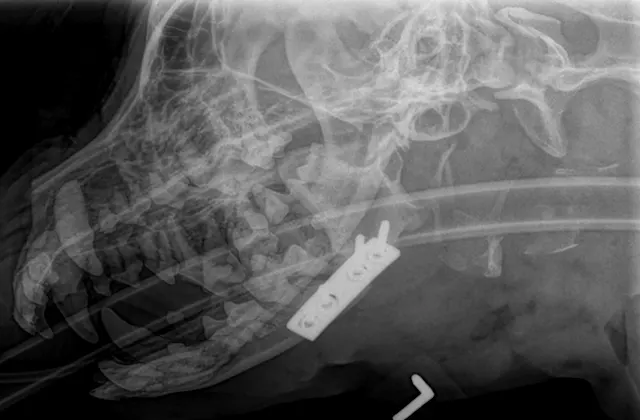

Lateral skull x-ray of dog with endotracheal tube in place and radiopaque cerclage wire around base of mandibular canines.

Lateral radiograph showing placement of a mandibular symphyseal wire in a dog

When managing fractures of the mandibular body, the surgeon’s goal is to provide stability to achieve bone union, whereas the dentist’s goal is to maintain tooth viability and proper occlusion. For example, a surgeon may want to place cerclage wires near the tooth root in the ventral mandible to secure good-quality bone at the tension surface, whereas a dentist might prefer an intraoral technique to preserve the root and relinquish a biomechanically superior location for implant placement. With proper planning, these goals can be balanced with a variety of methods. Interfragmentary wiring can be performed by placing 24- to 18-gauge wire throughout the length of the mandibular body; typically, >1 wire should be placed perpendicular to the fracture line for stability (Figure 3). Simple straight-line fracture configurations are best for this technique. In cases involving comminution of the mandible, plates or external fixators can be useful (Figures 4 and 5). These are typically placed on the lateral aspect of the mandible with careful avoidance of the tooth roots.